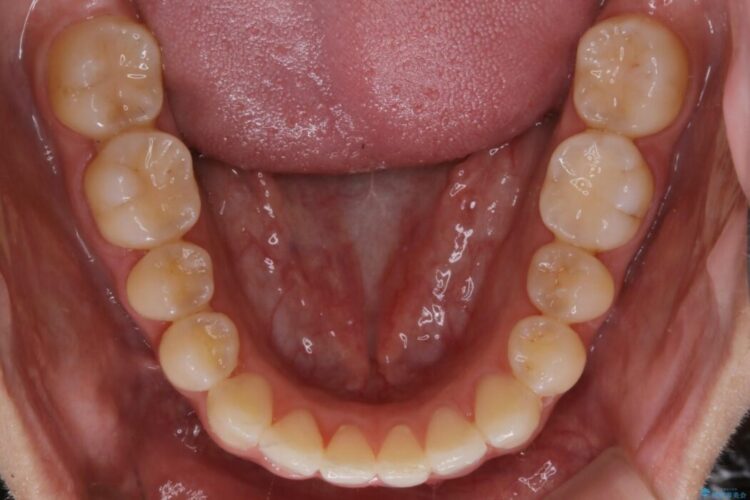

【20代女性】軽度の反対咬合を部分矯正でなおす

上顎歯列のガタガタを改善したいとのことで来院されました。

前歯の一部に反対咬合が見られ歯列がガタガタしていたためインビザラインでの矯正治療をご提案しました。

また、奥歯の噛み合わせなどにほとんど問題がなかったことからインビザラインのライトパッケージを選択しました。

反対咬合の歯も整ったアーチに収まり、きれいに仕上がりました。